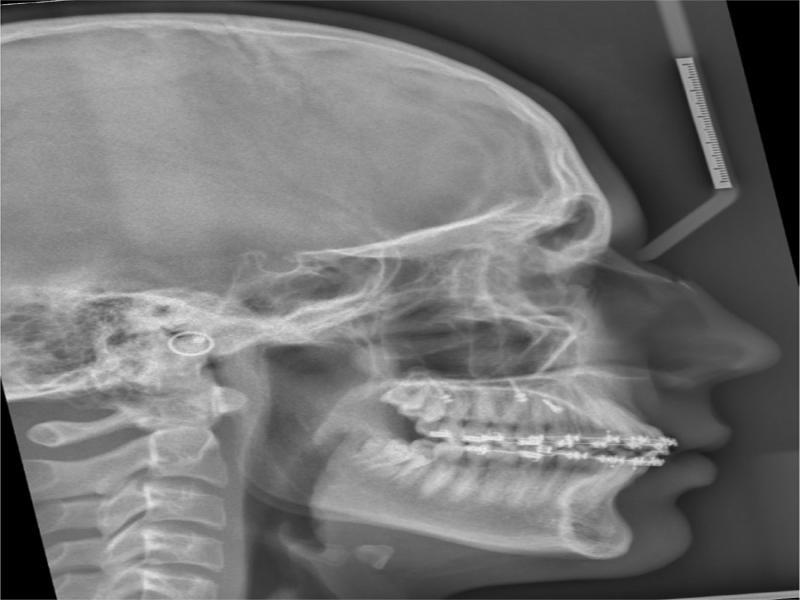

Figure 5.

Cephalometric summary

| Measurement | Std | Pre-Rx | Post-Rx | Change | |

|---|---|---|---|---|---|

| SKELETAL | |||||

| Maxilla | SNA | 82 | 88 | 88.3 | 0.3 |

| A Point Convexity | 3 | 2.9 | 2.5 | -0.4 | |

| NaVert - A point | 1 mm | 1.8 | 2.6 | 0.8 | |

| Mandible | SNB | 80 | 83.3 | 84 | 0.7 |

| Facial Angle | 87 | 88.9 | 92.2 | 3.3 | |

| NaVert - Po | -8 to -6 mm/-2 to 4 mm | -2.1 | 2.1 | 4.2 | |

| Basal Arch Relationship | ANB | 2 | 4.7 | 4.3 | -0.4 |

| WITS | F: 0 mm | 3.1 | 0 | -3.1 | |

| Vertical | Md Plane Angle | 26 | 20.9 | 18.7 | -2.2 |

| LFH Angle | 47 | 43.9 | 46.3 | 2.4 | |

| Md Arc | 26 | 37.1 | 39.8 | 2.7 | |

| Facial Axis Angle | 90 | 90.7 | 90.8 | 0.1 | |

| Jarabak ratio | 0.59.0.63 | 0.73 | 0.74 | 0.01 | |

| DENTAL | |||||

| Upper Incisors | UI to FH | 110° | 115.9 | 120.4 | 4.5 |

| UI to Pal Plane | 110° | 114.7 | 117.5 | 3.8 | |

| UI to Na Vert | 5 mm | 3.3 | 5 | 1.7 | |

| Lower Incisors | LI to Md Plane | 92.5° | 101.6 | 104.5 | 2.9 |

| LI to Apo | 22 | 28.2 | 31.7 | 3.5 | |

| LI to Apo | 1 | 2.7 | 4.5 | 1.8 | |

| Interincisal | UI to LI | 130 | 121.6 | 114.4 | -7.2 |

| SOFT TISSUE | L Lip - E Line | -2 | -2.4 | -1.1 | 1.3 |

| SnVert - U Lip | 1 mm | 2.2 | 3.3 | 1.1 | |

| SnVert - L Lip | -1 mm | -4.1 | 0.2 | 4.3 | |

| SnVert - Po' | -3 mm | -8.4 | -3.8 | 4.6 | |